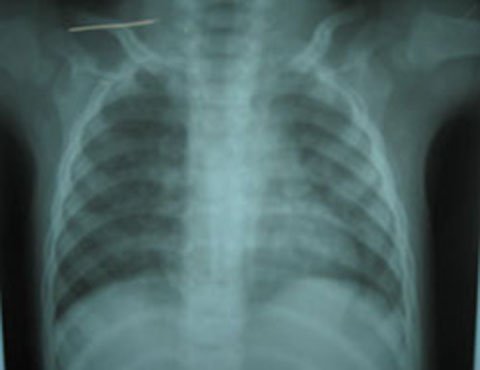

Tuy nhiên, sau khi chụp X – Quang, siêu âm và làm các xét nghiệm, bác sĩ của khoa Nội tổng quát phát hiện bé Q. bị xẹp phổi giữa bên thuỳ trái do một mảnh xương găm vào.

| Phim chụp X – Quang cho thấy phổi của bé Q. có vật lạ gây tổn thương. |

Bệnh nhi đã được tiến hành phẫu thuật nội soi, gắp ra một mảnh xương có kích thước 0,3 x 0,5 cm.